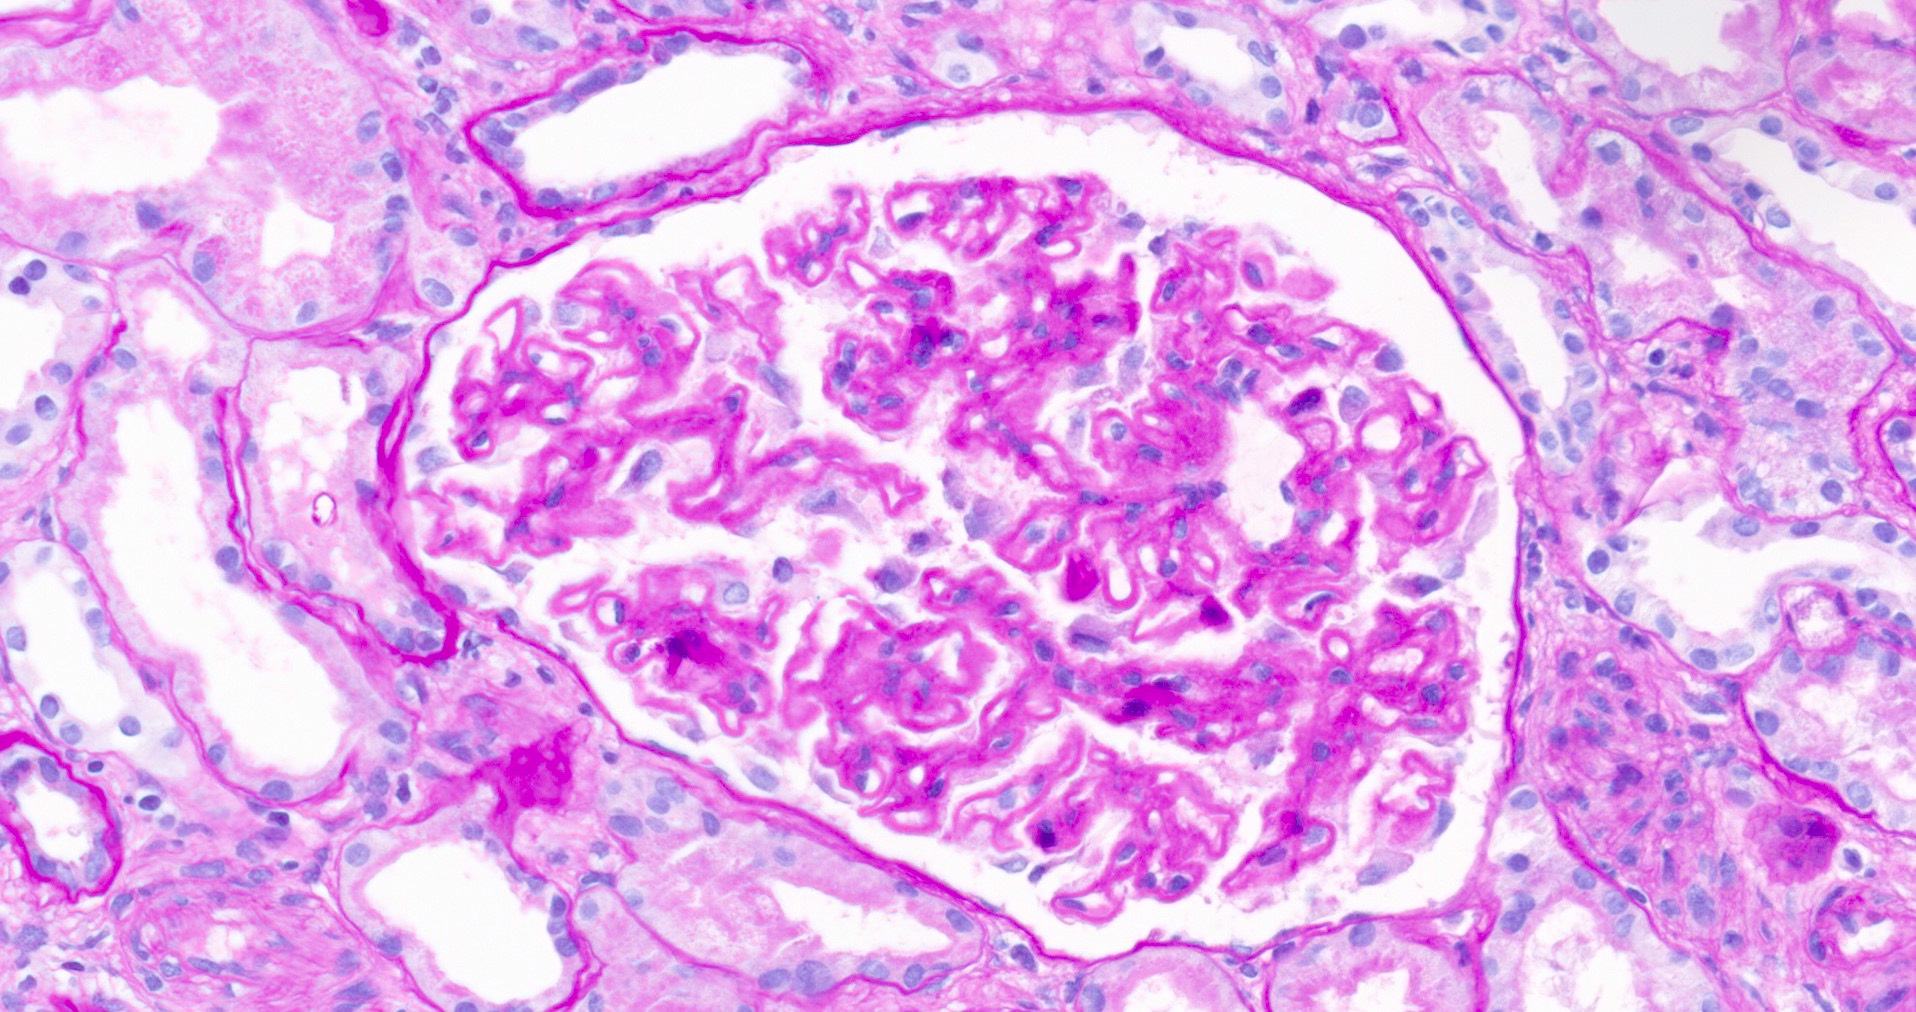

Microscopic (histologic) description

- Glomeruli may appear entirely normal in early disease (stage 1)

- Thickening of glomerular basement membrane

- Subepithelial spike formation or vacuolated appearance on PAS or Jones silver stain (Colvin: Diagnostic Pathology - Kidney Diseases, 2nd Edition, 2015, Zhou: Silva's Diagnostic Renal Pathology, 2nd Edition, 2017)

Microscopic (histologic) images

- Microscopic description: 18 glomeruli, 1 of these with global sclerosis. Thickening of the glomerular capillary wall. Presence of spikes and internal vacuolizations of the glomerular basement membrane evaluated by silver stain. No evidence of hypercellularity, crescent or necrosis. Fibrosis occupying < 10% of the interstitium.